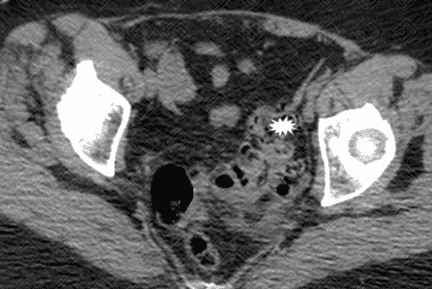

Texto alternativo para a imagem Figura 1. Créditos: Dra. Elazir Mota - Rio de Janeiro/RJ

Descrição das figuras 1 e 2: Tomografia computadorizada do abdome. Presença de alguns divertículos colônicos (figura 1 - asterisco), mais evidentes no sigmoide, no qual observa-se densificação dos planos adiposos e lâmina líquida de permeio (figura 2 - setas vermelhas). Achados compatíveis com diverticulite aguda não complicada do sigmoide.